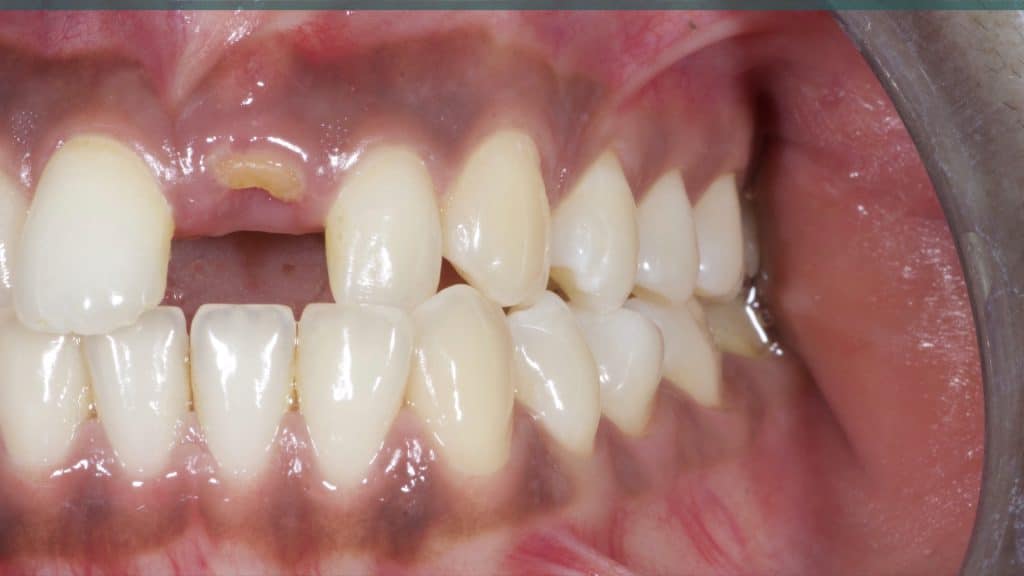

20 days post-op after suture removal